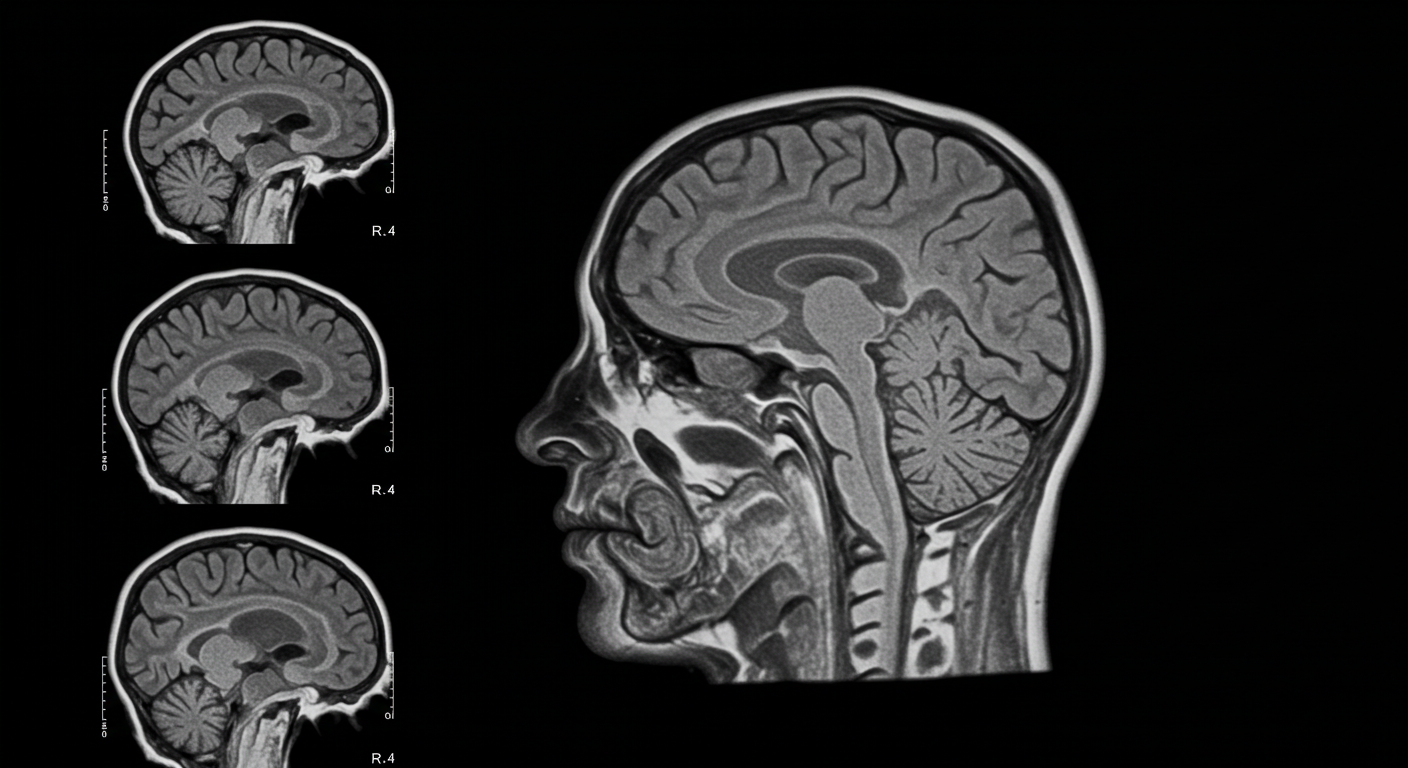

현대 신경영상학 기술의 발달로 우리는 마음챙김 수련이 뇌에 미치는 물리적 변화를 실시간으로 관찰할 수 있게 되었습니다. 이러한 변화들은 단순한 일시적 효과가 아닌, 뇌의 구조적 재편성을 의미하는 신경가소성의 결과입니다.

사라 래자(Sara Lazar) 박사팀이 실시한 8주간의 마음챙김 기반 스트레스 감소(MBSR) 프로그램 연구에서, 참가자들의 전전두엽 피질 회백질 밀도가 평균 5.2% 증가하는 것으로 나타났습니다. 이는 MRI 스캔을 통해 측정된 객관적이고 정량적인 결과입니다.